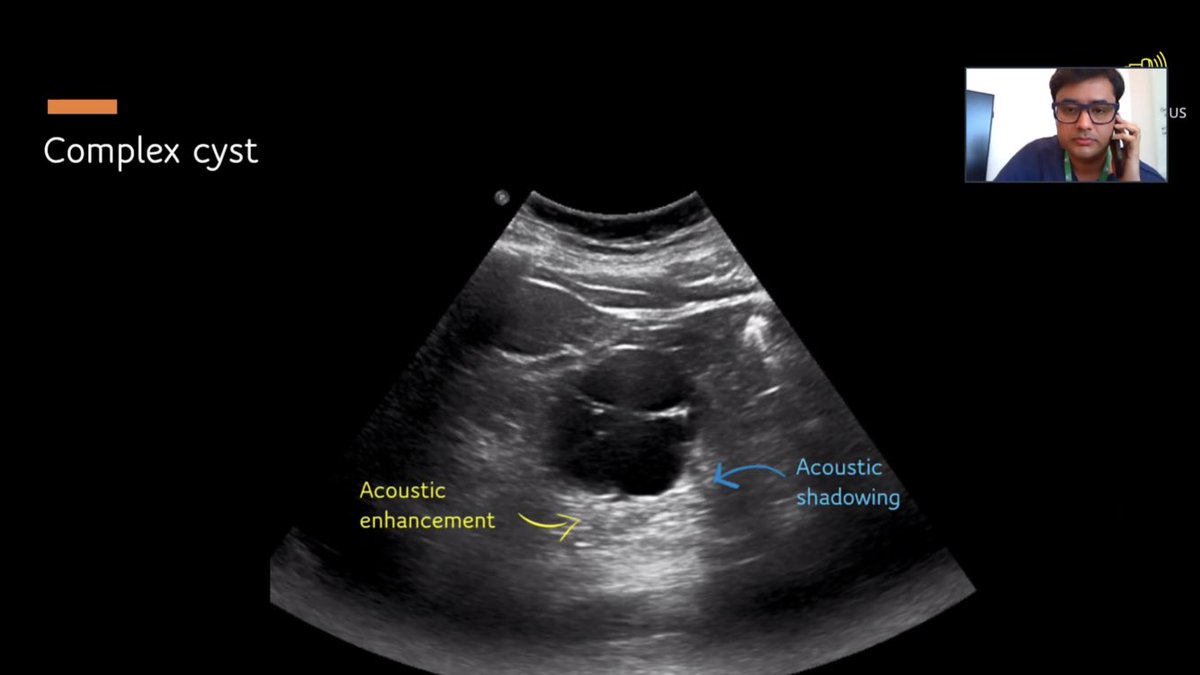

When you see cysts - you should see acoustic enhancement!

Complex cysts might have some calcifications and see acoustic shadowing

Take a look!